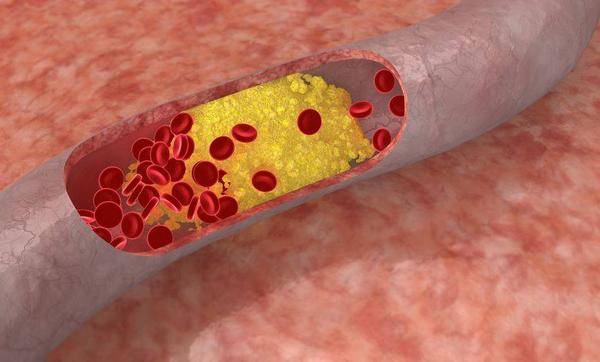

「蚯蚓腿」指的是下肢靜脈曲張,是由於下肢表淺靜脈的瓣膜功能出現障礙,導致靜脈當中的血液反流;

並隨著靜脈內壓力升高,以及靜脈內血液淤滯,使得靜脈壁出現過度膨脹、迂曲、擴張,並形成的團塊狀或條索狀現象。